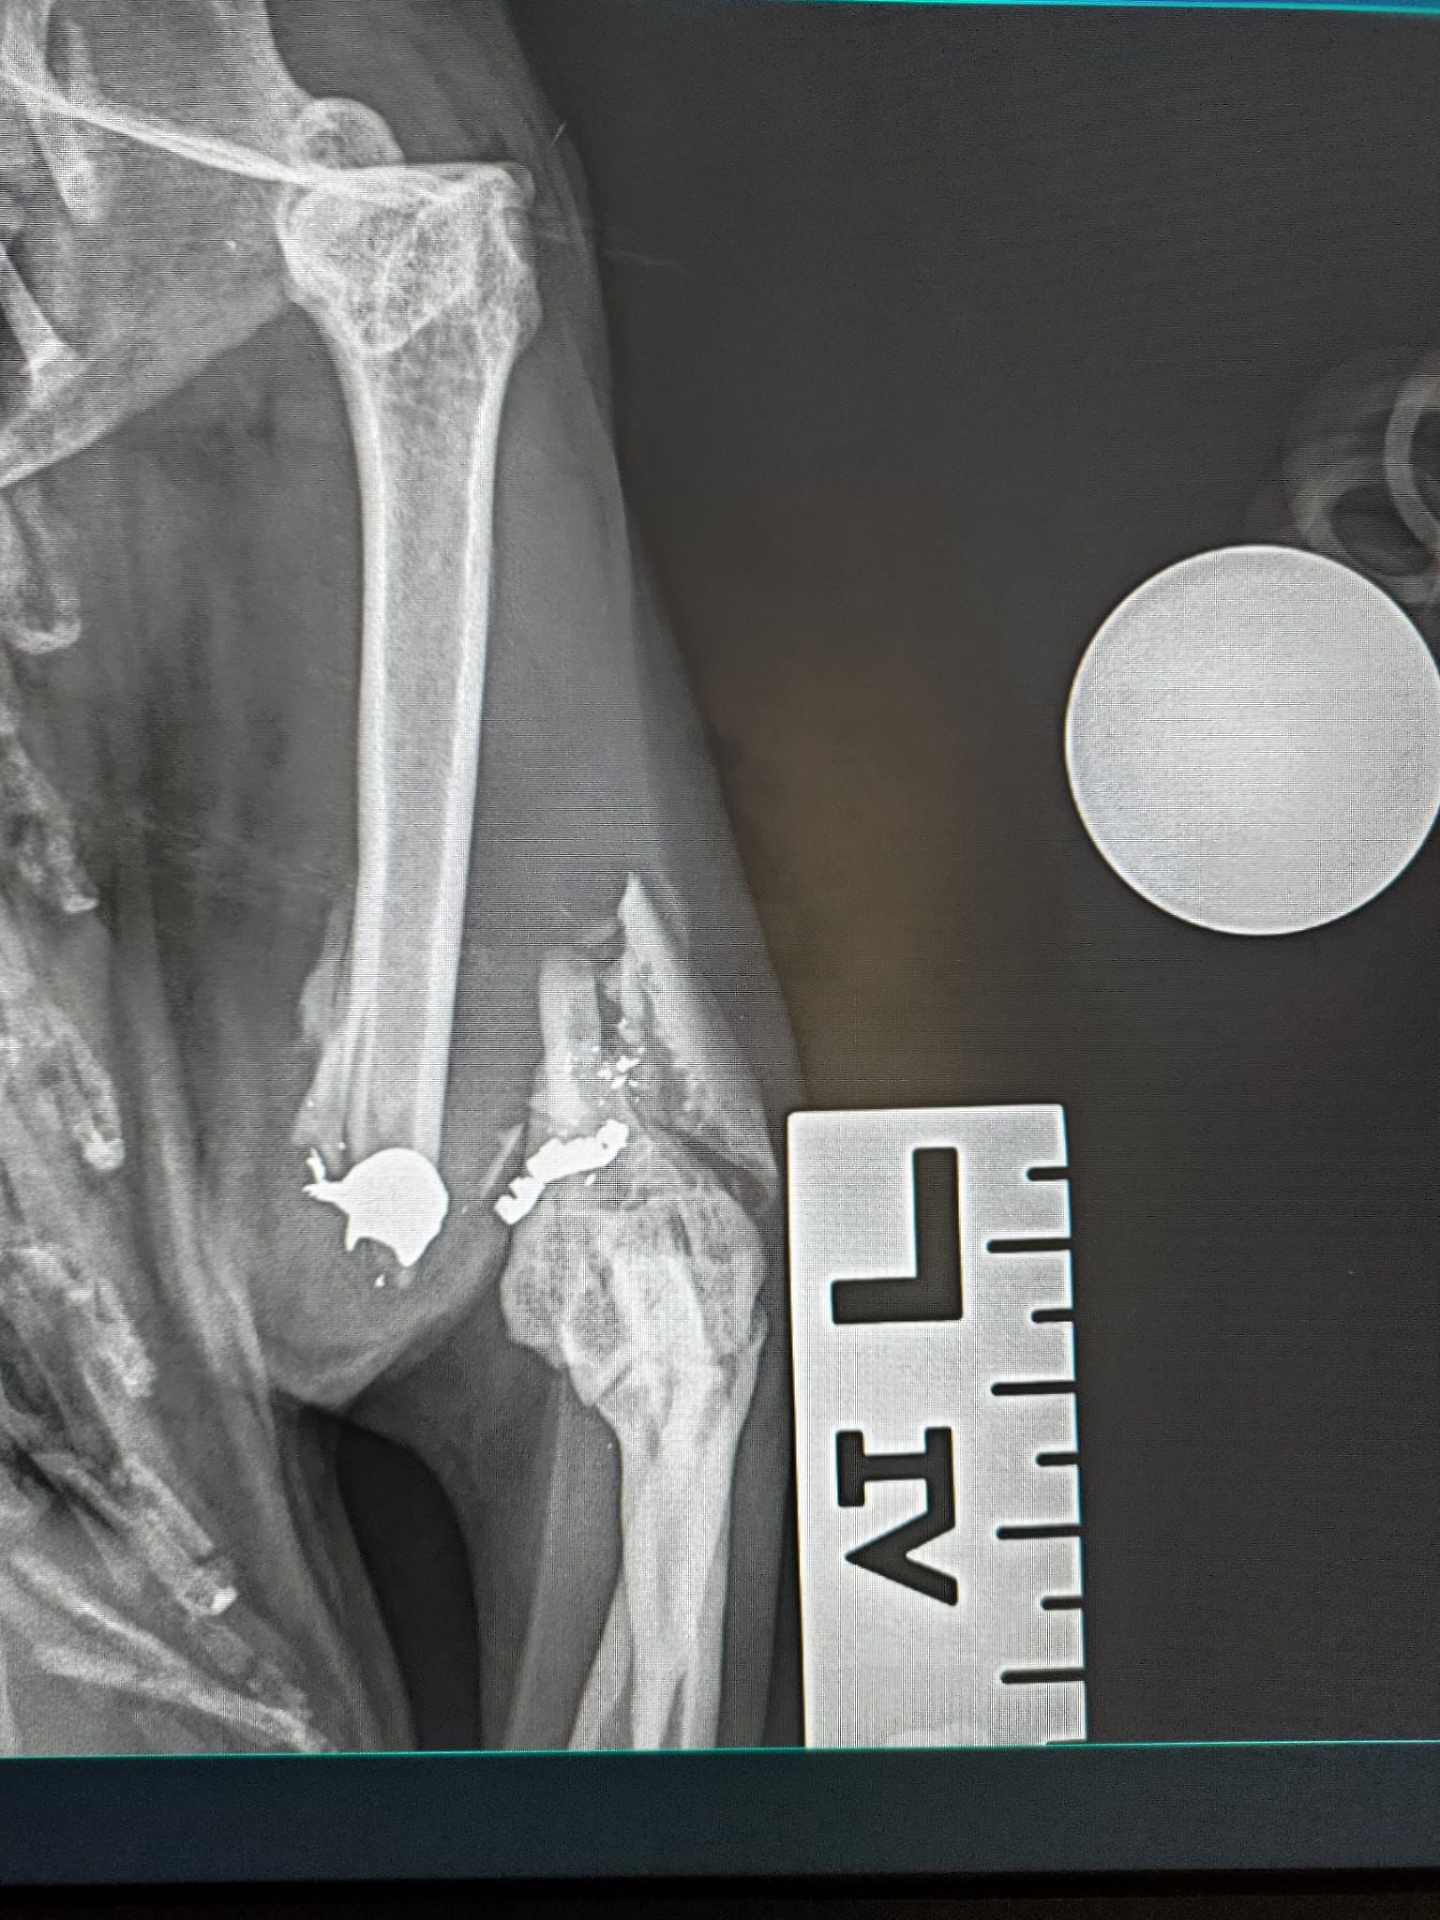

I pallini che hanno raggiunto il felino

Una delle due ha una zampa gravemente compromessa, "ma grazie all’impegno e alla professionalità dei dottori Laura Benedetti e Federico Vegni si sta lavorando per far arrivare una protesi speciale che possa permetterle di tornare a vivere con dignità", dicono dallo Scudo di Pan.

La situazione dell’altra gatta - fanno sapere - è ancora più critica: oltre alla zampa seriamente danneggiata, presenta numerosi pallini di piombo nel corpo. I veterinari stanno valutando con grande attenzione come intervenire per salvarle la vita.